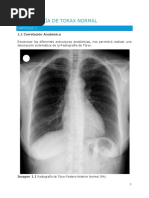

 Radiografía de tórax

o Permite valorar patrones radiológicos y esta a su vez relacionar con la etiología y

localización

o Las atelectasias segmentarias o imágenes alveolares pueden ser por sangre

aspirada.

o Patrón es bilateral queda la duda

o 20 – 40% de casos la Rx. puede ser normal

Algunos patrones radiológicos en pacientes con hemoptisis, y sus po sibles causas

Por todo ello el examen físico y la radiografía de tórax en un 50 – 60 % aportan información poco

valorable o errónea en los pacientes con hemoptisis